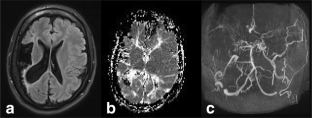

Moyamoya angiopathy is a rare vasculopathy with stenosis and/or occlusion of bilateral intracranial parts of internal carotid arteries and/or proximal parts of middle and anterior cerebral arteries. PHACE syndrome is characterized by large segmental hemangiomas in the cervical-facial region. Both conditions are known to be associated in rare cases. Recently, it was discussed in the literature that RNF213 variants could be etiologically involved in this association. Here, we describe a childhood case with this rare co-occurrence in which we did not identify any rare RNF213 variant. The clinical and genetic backgrounds are discussed.

Fig. 1

Fig. 2